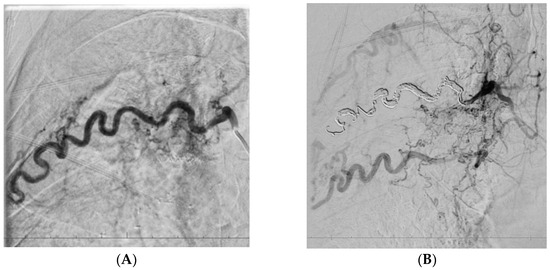

Cystic Artery Bleeding: Imaging Insights and Systematic Review of Endovascular Management

Background: Cystic artery bleeding (CAB) is a rare but potentially life-threatening condition. Its etiologies span iatrogenic trauma, inflammatory diseases, and trauma, often presenting variably as hemoperitoneum, upper gastrointestinal bleeding, or hemorrhagic shock. The clinical heterogeneity of CAB complicates its diagnosis, necessitating a high index of suspicion and reliance on imaging modalities, particularly computed tomography (CT), for accurate identification of bleeding sources and differentiation from other causes of abdominal pain. Methods: This pictorial essay highlights key imaging findings in CAB and pseudoaneurysms, emphasizing the role of ultrasound, CT, and digital subtraction angiography (DSA) in diagnosis and management planning. Additionally, a systematic review of transcatheter arterial embolization (TAE) is presented, consolidating data from 64 studies encompassing 90 patients. Results: The review evaluates patient demographics, etiologies, clinical presentations, and procedural outcomes, underscoring TAE’s high efficacy and safety as a first-line treatment. Conclusions: The findings reinforce the importance of early diagnosis and tailored intervention strategies to optimize outcomes in CAB management. Full article

Show Figures

Figure 1